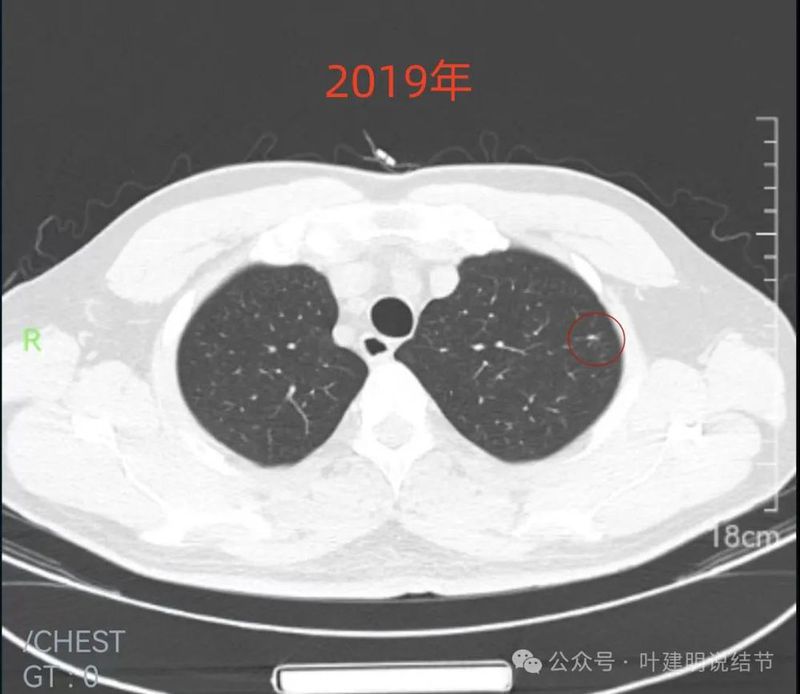

2019年9月时右中叶磨玻璃密度病灶,轮廓与边界清楚,没有实性成分,中间密度稍低,考虑肿瘤范畴的,原位癌或微浸润性腺癌可能性较大。

2019年9月左上叶的磨玻璃结节,轮廓稍显模糊,有血管贴边,膨胀性不足。似乎更符合良性点。

病灶处密度过高,似偏长条状。

此层见病灶有磨玻璃成分,但显得较为模糊。